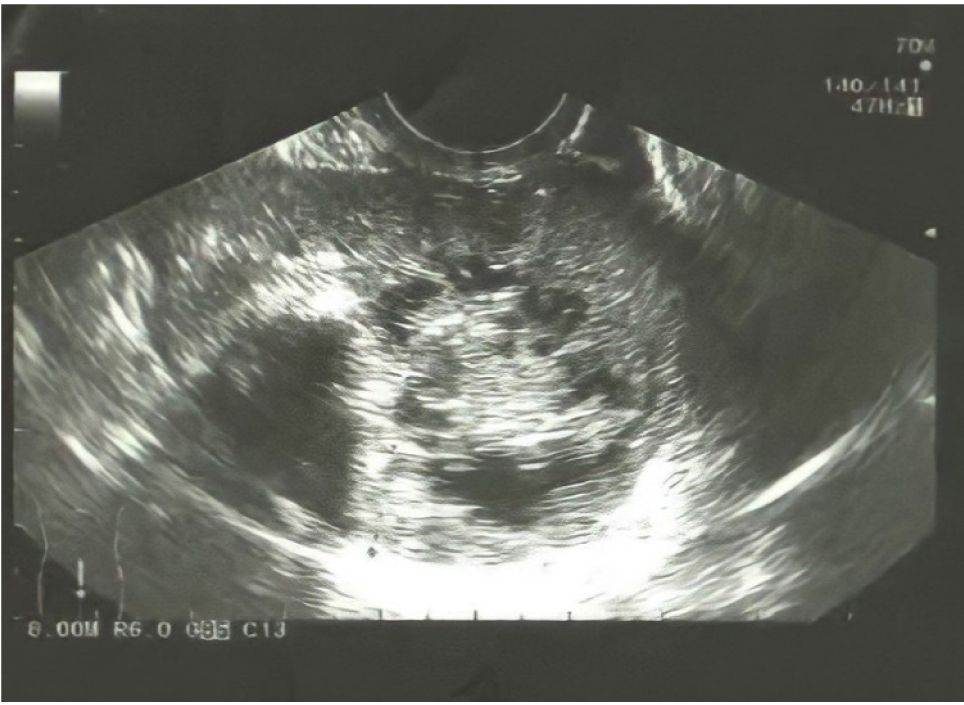

Пациентка К., 20 лет, обратилась к врачу-гинекологу с жалобами на боль во время полового акта и менструации. По результатам УЗИ (рис. 1): патологическое гетерогенное образование с ровными контурами и гипоэхогенным содержимым в позадиматочном пространстве, кровоток не регистрировался.

Рис. 1. Патологическое гетерогенное образование с ровными контурами и гипоэхогенным содержимым в позадиматочном пространстве, кровоток не регистрируется